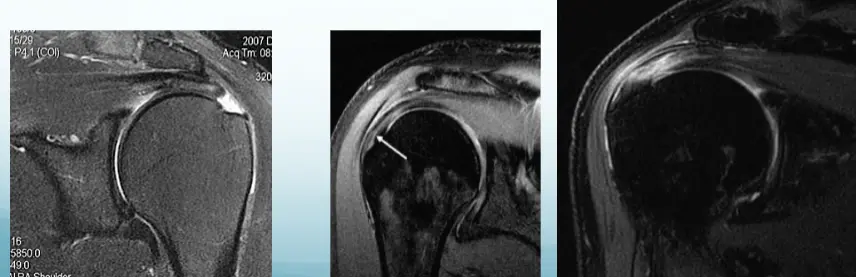

- MRI:

- Bursitis / Thickening of tendon

Imaging

- MRI – image of choice